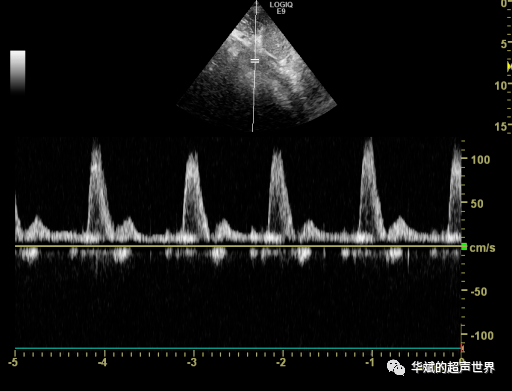

请不要轻信目测的血流信号(一) --cdfi我不想背黑锅,频谱形态很重要

有切迹或者双向血流信号一定是盗血吗?